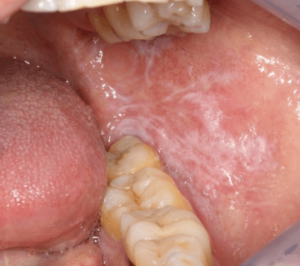

この白い線の正体は、専門用語で「頬粘膜圧痕・頬圧痕(きょうねんまくあっこん・きょうあっこん)」や「白線(はくせん)」と呼ばれるものです。実はこれ、決して珍しいものではなく、ある調査では成人の半数近くに見られるというデータもあるほど、ごくありふれたお口の現象なのです。

頬圧痕は、頬の粘膜のうち、ちょうど上の歯と下の歯が噛み合う位置(咬合平面)に沿って現れます。

- 白い線状に、少し盛り上がっている

- 舌で触れると、少し硬い感触やザラつきがある

- 歯の並びに合わせて、波打った形をしていることがある

- 基本的には痛みやしみる症状はない

主なメカニズムは、粘膜への「慢性的な物理刺激」による「過角化(かかくか)」です。 わかりやすく言えば、「お口の中にできたタコ」のようなものです。手や足に靴擦れやペンだこができるのと同じ原理で、頬の柔らかい粘膜が、歯によって長時間圧迫されたり擦れたりすることで、防御反応として皮膚(角質)が厚く硬くなります。その厚くなった部分が白く見えているのです。

- 白い線がレース状(網目状)の模様になっている